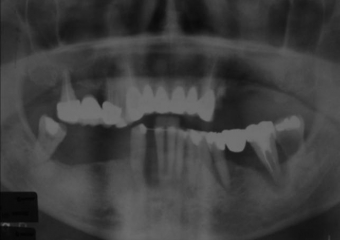

Raio X inicial